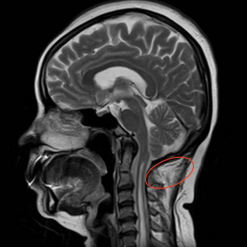

刘女士一家觉得颈椎手术风险太大,保险起见,刘女士慕名找到betway在线登陆周围神经修复外科,希望靠手外科医生丰富的门诊经验帮她解决这一难题。手外科陈步国主任不单纯考虑是肘管综合征,随后便让刘女士拍了头颈部核磁,这才发现刘女士竟患有“脊髓空洞症”。随后陈主任对刘女士这一情况启动了多学科会诊,结合影像资料,终于找到真凶,原来这的确不是单纯的肘管综合征,也不是所谓的颈椎病,而是颅底凹陷症。

据神经外科郭宗扬主任介绍,颅底凹陷症不多见,这主要还是因为大脑内中枢神经先天性受到压迫,致使大脑部分区域“工作失灵”。

术前,郭宗扬教授和神经外科董伟主任带领团队制定了周密的手术计划,决定为患者施行“开颅后颅窝减压术”。术中在郭宗扬教授的指导下,神经外科董伟主任娴熟的避开椎动脉,保护好脊髓,使用超声铣刀将寰椎后弓切除、枕骨大孔扩大,后颅窝充分减压,患者的“生命通道”被重新打开,受压的脊髓重新膨起,出血仅100毫升,所有的医护终于松了一口气。

专家提醒,如果出现行走不稳、肢体麻木无力等症状,不仅要考虑常见的腕\肘管综合征、颈椎病、腰椎间突出症等,也要当心颅底凹陷症。据郭教授介绍,齿状突向后向上的病人要前入路(从口腔),而这个病人是寰枕融合畸形,是从延髓的后方向前压迫而造成的症状。若患者颈部疼痛、四肢乏力、麻木、四肢或者双下肢感觉分离即疼温觉减退,触觉存在,应考虑合并脊髓空洞症。尽管它的发病率不高,但会引起严重的后果。要早发现、早诊断、早治疗,不要病急乱投医以延误病情。